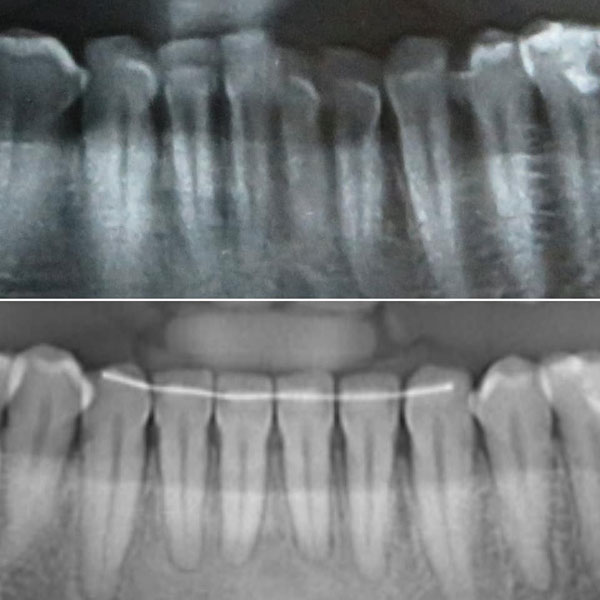

Perfect root paralleling on the X rays |